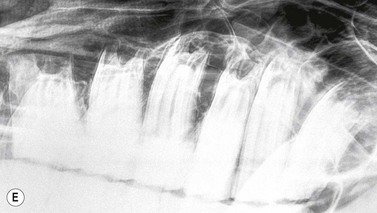

image image image image image image

Fig. 13.41 Radiographic signs of periapical infection. (A) Radiolucent halos are evident around both roots of an infected 408, with widening of periodontal space, sclerosis of the ventral mandibular cortex and periosteal new bone deposition. (B) A zone of sclerosis is present around this infected 306. The affected apex is somewhat blunter than those of adjacent teeth; however, this can be a normal feature of 06s. An arrow points to a small radio-opaque marker placed on the skin at the site of facial swelling. (C) Infected 108. A periapical radiolucent halo surrounded by marked sclerosis is evident around the infected apex of this tooth, which lies outwith the rostral maxillary sinus in this horse. (D) Gross destruction of the architecture of this infected 407 dental bud is present, with loss of much of the apical aspect of its crown. Multiple radio-opaque fragments are present in the alveolus, which may represent dental fragments or cementoma formation. A draining tract (with probe inserted) and gross mandibular new bone formation are evident. (E) Marked sclerosis is present around an apically infected 210. This horse had concurrent sinusitis. (F) Massive reactive cementoma deposition is present around the apex of chronically infected 207. Dystrophic calcification of the nasal conchae is likely also contributing to the radio-opaque appearance in the area rostral to the alveolus of 207. Most of the reserve crown of this tooth was still present; however, it is quite radiolucent, due to demineralization caused by chronic infection.

Radiographic changes consistent with early periapical infection include widening of the periodontal space and focal loss or irregularity of the lamina dura. When periapical infection has been present for many weeks, the affected apex and adjacent alveolar bone develop lytic changes, especially in mature teeth where the true roots (non-enamel areas) are well formed, due to decalcification and/or destruction of dental and adjacent alveolar tissues. These changes manifest as periapical radiolucent ‘halos’, and with time, a rounded or ‘clubbed’ appearance of the tooth roots can develop due to gross lysis/destruction of the root structures. In more chronic periapical infection, a zone of radiodense sclerosis may surround the periapical ‘halo’, due to new bone deposition around the lytic infected dental/alveolar area. More marked sclerosis develops around the apices of the rostral maxillary and mandibular cheek teeth than around the apices of the caudal maxillary cheek teeth, because the apices of the former teeth are positioned in denser bone than those of the caudal maxillary cheek teeth, which are situated in only thin alveolar bone within the maxillary sinuses.